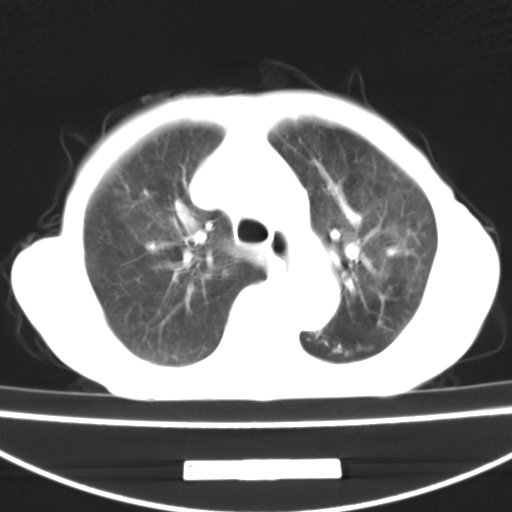

患者 女 67岁,反复咳嗽咳痰2年,加重伴喘及双下肢浮肿1月

诸大血管及f肺门血管增粗迂曲.左下肺多发薄壁空腔影.部分非也透亮度增高.薄曾扫描可区分肺气肿类型.考虑1.慢性支气管炎 2.左下肺支气管扩张 3.肺气肿 4 肺动脉高压5.是否有先心病病史

考虑1.慢性支气管炎 2.左下肺支气管扩张 3.肺气肿 4 肺动脉高压

慢支炎、肺气肿、双肺感染、左下囊状支扩。

慢支、肺气肿、肺动脉高压;左下肺囊状支扩并粘液栓形成。